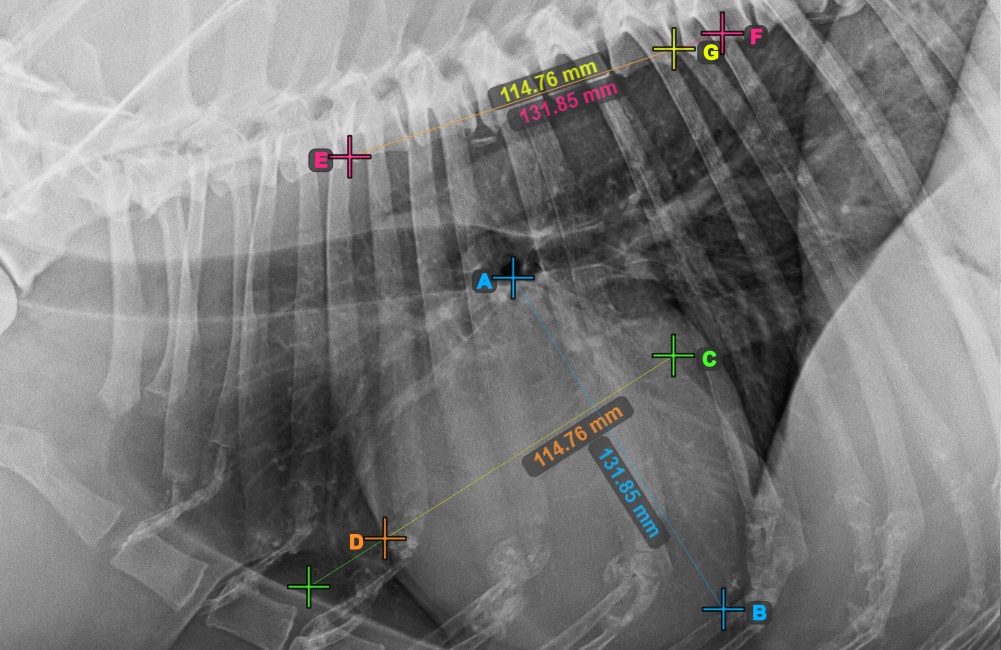

Identify the beginning of the T4 vertebra (the fourth vertebral body of the spine), counting from the initial point of the spine. Mark the beginning of the T4 vertebrae to continue the measurement. The software will draw lines from the marked point along the spine. The length of the lines depends on the measured long and short axes of the heart.

The image below represents the typical placement of the point at the beginning of the fourth vertebral body of the spine.